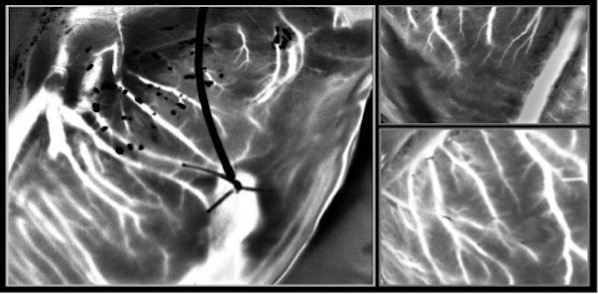

据《生物医学光学杂志》(jbo)报道,由法国巴黎萨克雷大学的伊莉斯·科林(elise colin)教授领导的一个研究小组引入了一种安全、无创的光学技术,可以在eshp期间对供体心脏的冠状动脉血液循环进行成像。该方法利用了最近开发的散斑成像技术,即激光散斑正交对比成像(lsoci),该技术被开发用于检测运动红细胞的多次散射。

在这项研究中,研究人员提高了lsoci观察心脏小血管的成像能力。因此,所提出的方法使用特定的偏振滤波过程来分析心脏中的血流,该过程允许抑制表面散射。因此,用于成像过程的时变散斑图案主要是通过外周血管内运动的红细胞上的多次散射产生的。

科林说:“光学技术可以实时对心脏的整个外周血管系统进行高分辨率成像。”

为了克服由于心脏跳动而导致的跟踪脉管系统的挑战,研究人员用一种名为多周期增强信噪比(mpe-snr)的方法进一步优化了这项技术。随着时间的推移,他们拍摄了一系列图像,构建了一组框架,描绘了类似心脏位置的脉管系统。然后使用其他图像对该序列中的每个图像进行优化,以减少噪声并增强细节。优化后的图像代表了不同时间点的血管系统,研究人员使用一系列这样的图像在几秒钟内将小到100微米的血管可视化。